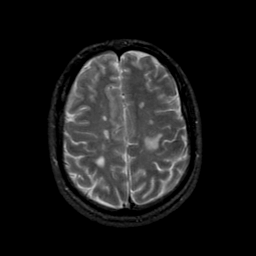

MR Study #21, November 3, 1991 -- Slice #37